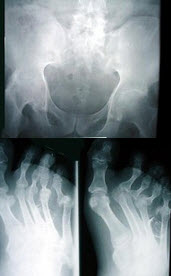

3、单项选择题

男,45岁,双足肿痛,晨僵,结合图像,最可能的诊断是()

A.关节结核

B.痛风性关节炎

C.类风湿关节炎

D.牛皮癣性关节炎

E.Reiter综合征